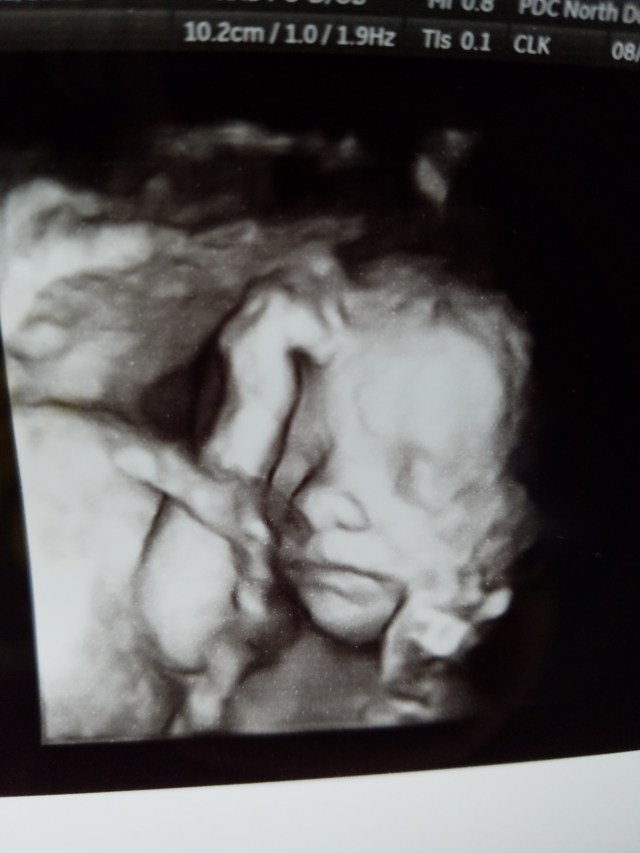

18 Weeks!